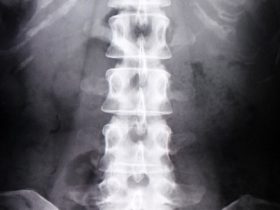

背骨の歪みを治す6つの治し方と整骨院の専門家が行う治療方法

「背骨の歪みを治す6つの治し方と整骨院の専門家が行う治療方法」 背骨とは、椎骨と椎間板で構成されている脊椎を指します。 健康な人の脊椎を横から見ると、S字上の緩やかな曲線になります。 この脊椎のカーブは… -